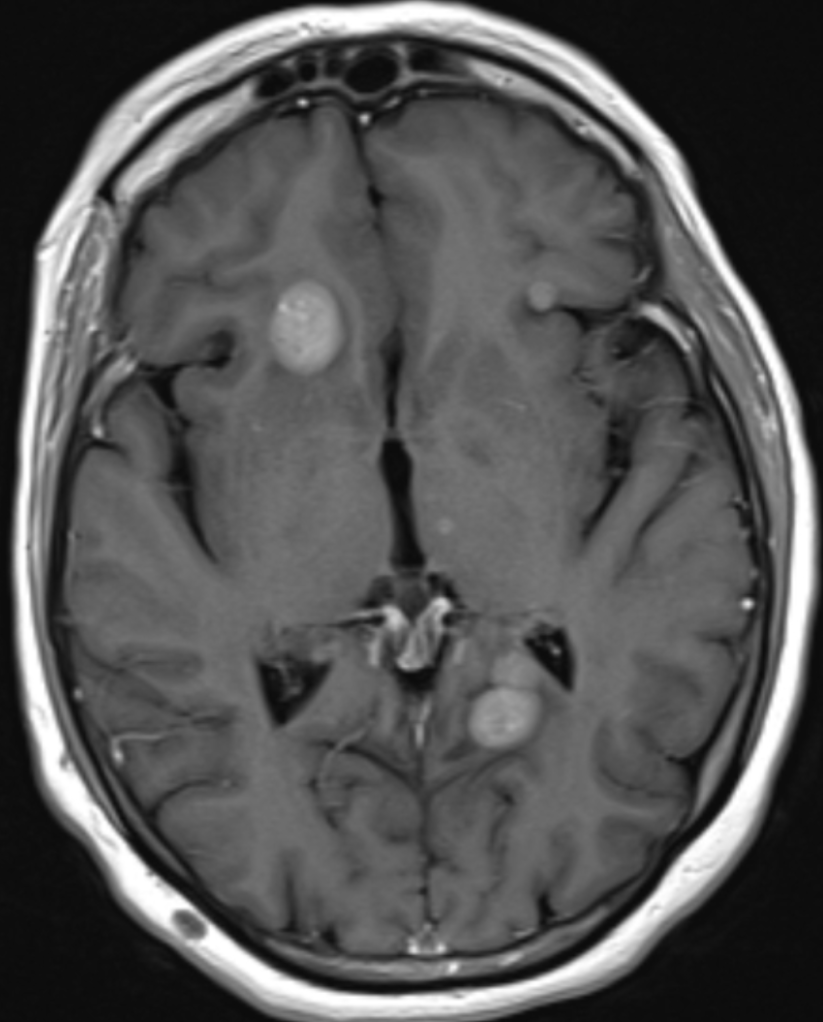

Magnetic Resonance Imaging (MRI) scans can take 20 minutes to an hour, depending on the area being scanned and how many different images the doctors want to see. As the name indicates, there is a large magnet that forces all the water molecules in your body to be aligned to the same field. Then loud bursts of radiofrequency energy are used to disrupt the alignment in the area being scanned (you will be given ear plugs). As the water molecules re-align back to the magnetic field, they release radiowaves that are detected to make an image. Muscle, bone, body fluids, and fat all give different signals and we can get better contrast with MRI than CT scans. MRIs are most often used to image the brain, spinal cord, or abdomen where CT can’t distinguish all the different organs as well.